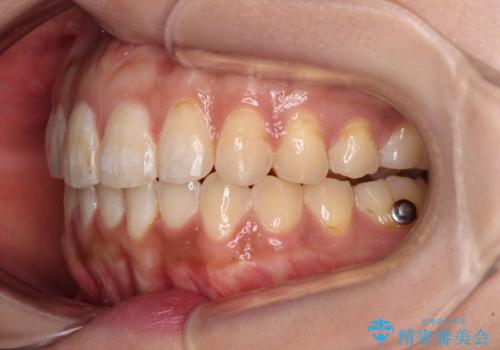

- 前歯のデコボコと上下前歯の隙間を気にして来院された患者様です。

下顎前歯はデコボコのため、歯肉が腫れやすくなっていました。

また、舌突出癖のため、上下前歯の間に隙間ができてしまい、上顎前歯が前方に傾斜している状態でした。

舌突出癖改善のためのトレーニングを行いながら、インビザラインにて矯正治療を行うこととしました。

舌のトレーニングをしっかりと行っていただき、上下前歯をしっかりと接触させることができました。

咬合力が強いため、治療途中に奥歯が咬み合わない期間が続きましたが、上下の奥歯でゴムかけを行っていただき、違和感なく咬み合うように仕上げることができました。